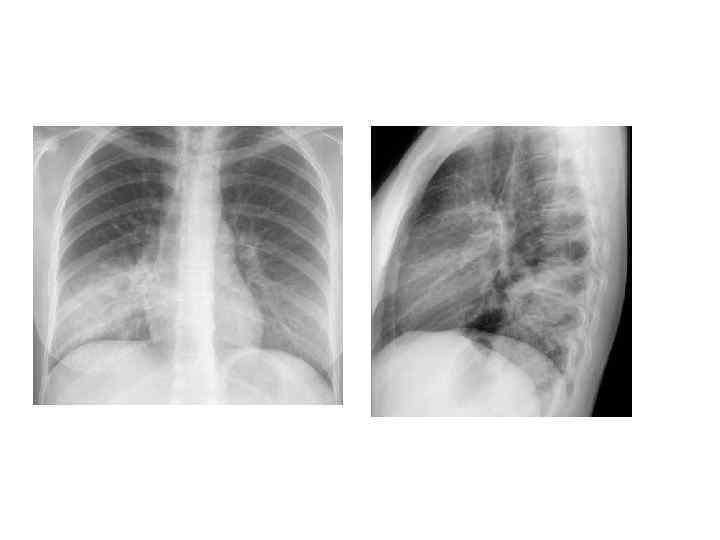

Рентгенологическая диагностика ВП • Рентген ОКГ является обязательным методом подтверждения диагноза пневмонии • Рентген ОКГ в двух проекциях должен быть проведен быстро при клиническом подозрении на пневмонию • Рентгенологический признак пневмонии – появление очаговой инфильтрации в легких

Критерии тяжелого течения ВП • • • Двух- и многодолевое поражение ОДН (Ра. О 2 < 60 мм рт. ст. или Sat 02 < 90%) Шок (снижение АД <90/60) ОПН Нарушение сознания

Критерии эффективности АБТ • • • Температура менее 37, 5 Нет интоксикациии Нет ДН (ЧСС менее 20) Нет гнойной мокроты Нет лейкоцитоза Нет отрицательной динамики по R